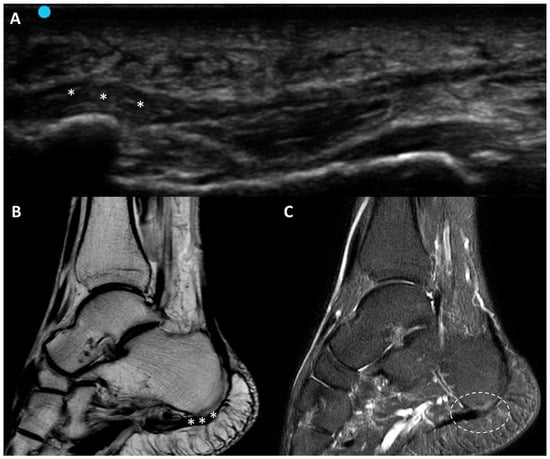

3.5.6. Plantar Fascial Rupture

- Pirri, C.; Stecco, C.; Pirri, N.; De Caro, R.; Özçakar, L. Ultrasound examination for a heel scar: Seeing/treating the painful superficial fascia. Med. Ultrason. 2022, 24, 255–256. [Google Scholar] [CrossRef] [PubMed]

- Slayton, M.H.; Amodei, R.C.; Compton, K.B.; Cicchinelli, L.D. Retrospective Analysis of Plantar Fascia by Ultrasound Imaging in Patients with Plantar Fasciitis. J. Am. Podiatr. Med. Assoc. 2018, 108, 349–354. [Google Scholar] [CrossRef] [PubMed]

- Parkm, Y.H.; Kim, H.J.; Kim, W.; Choi, J.W. Reliability of Ultrasound Measurement of Plantar Fascia Thickness: A Systematic Review. J. Am. Podiatr. Med. Assoc. 2023, 113, 21–24. [Google Scholar] [CrossRef] [PubMed]

- Khammas, A.S.A.; Mahmud, R.; Hassan, H.A.; Ibrahim, I.; Mohammed, S.S. An assessment of plantar fascia with ultrasound findings in patients with plantar fasciitis: A systematic review. J. Ultrasound 2023, 26, 13–38. [Google Scholar] [CrossRef] [PubMed] [PubMed Central]